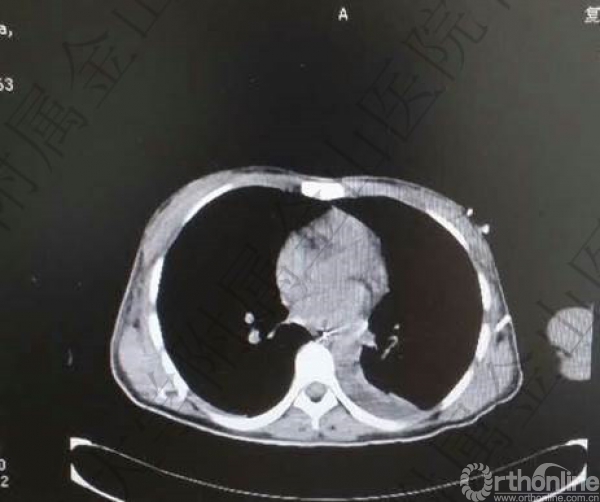

头胸腹CT未见明显实质脏器损伤,骨盆多发骨折:右侧髋臼骨折(双柱)。